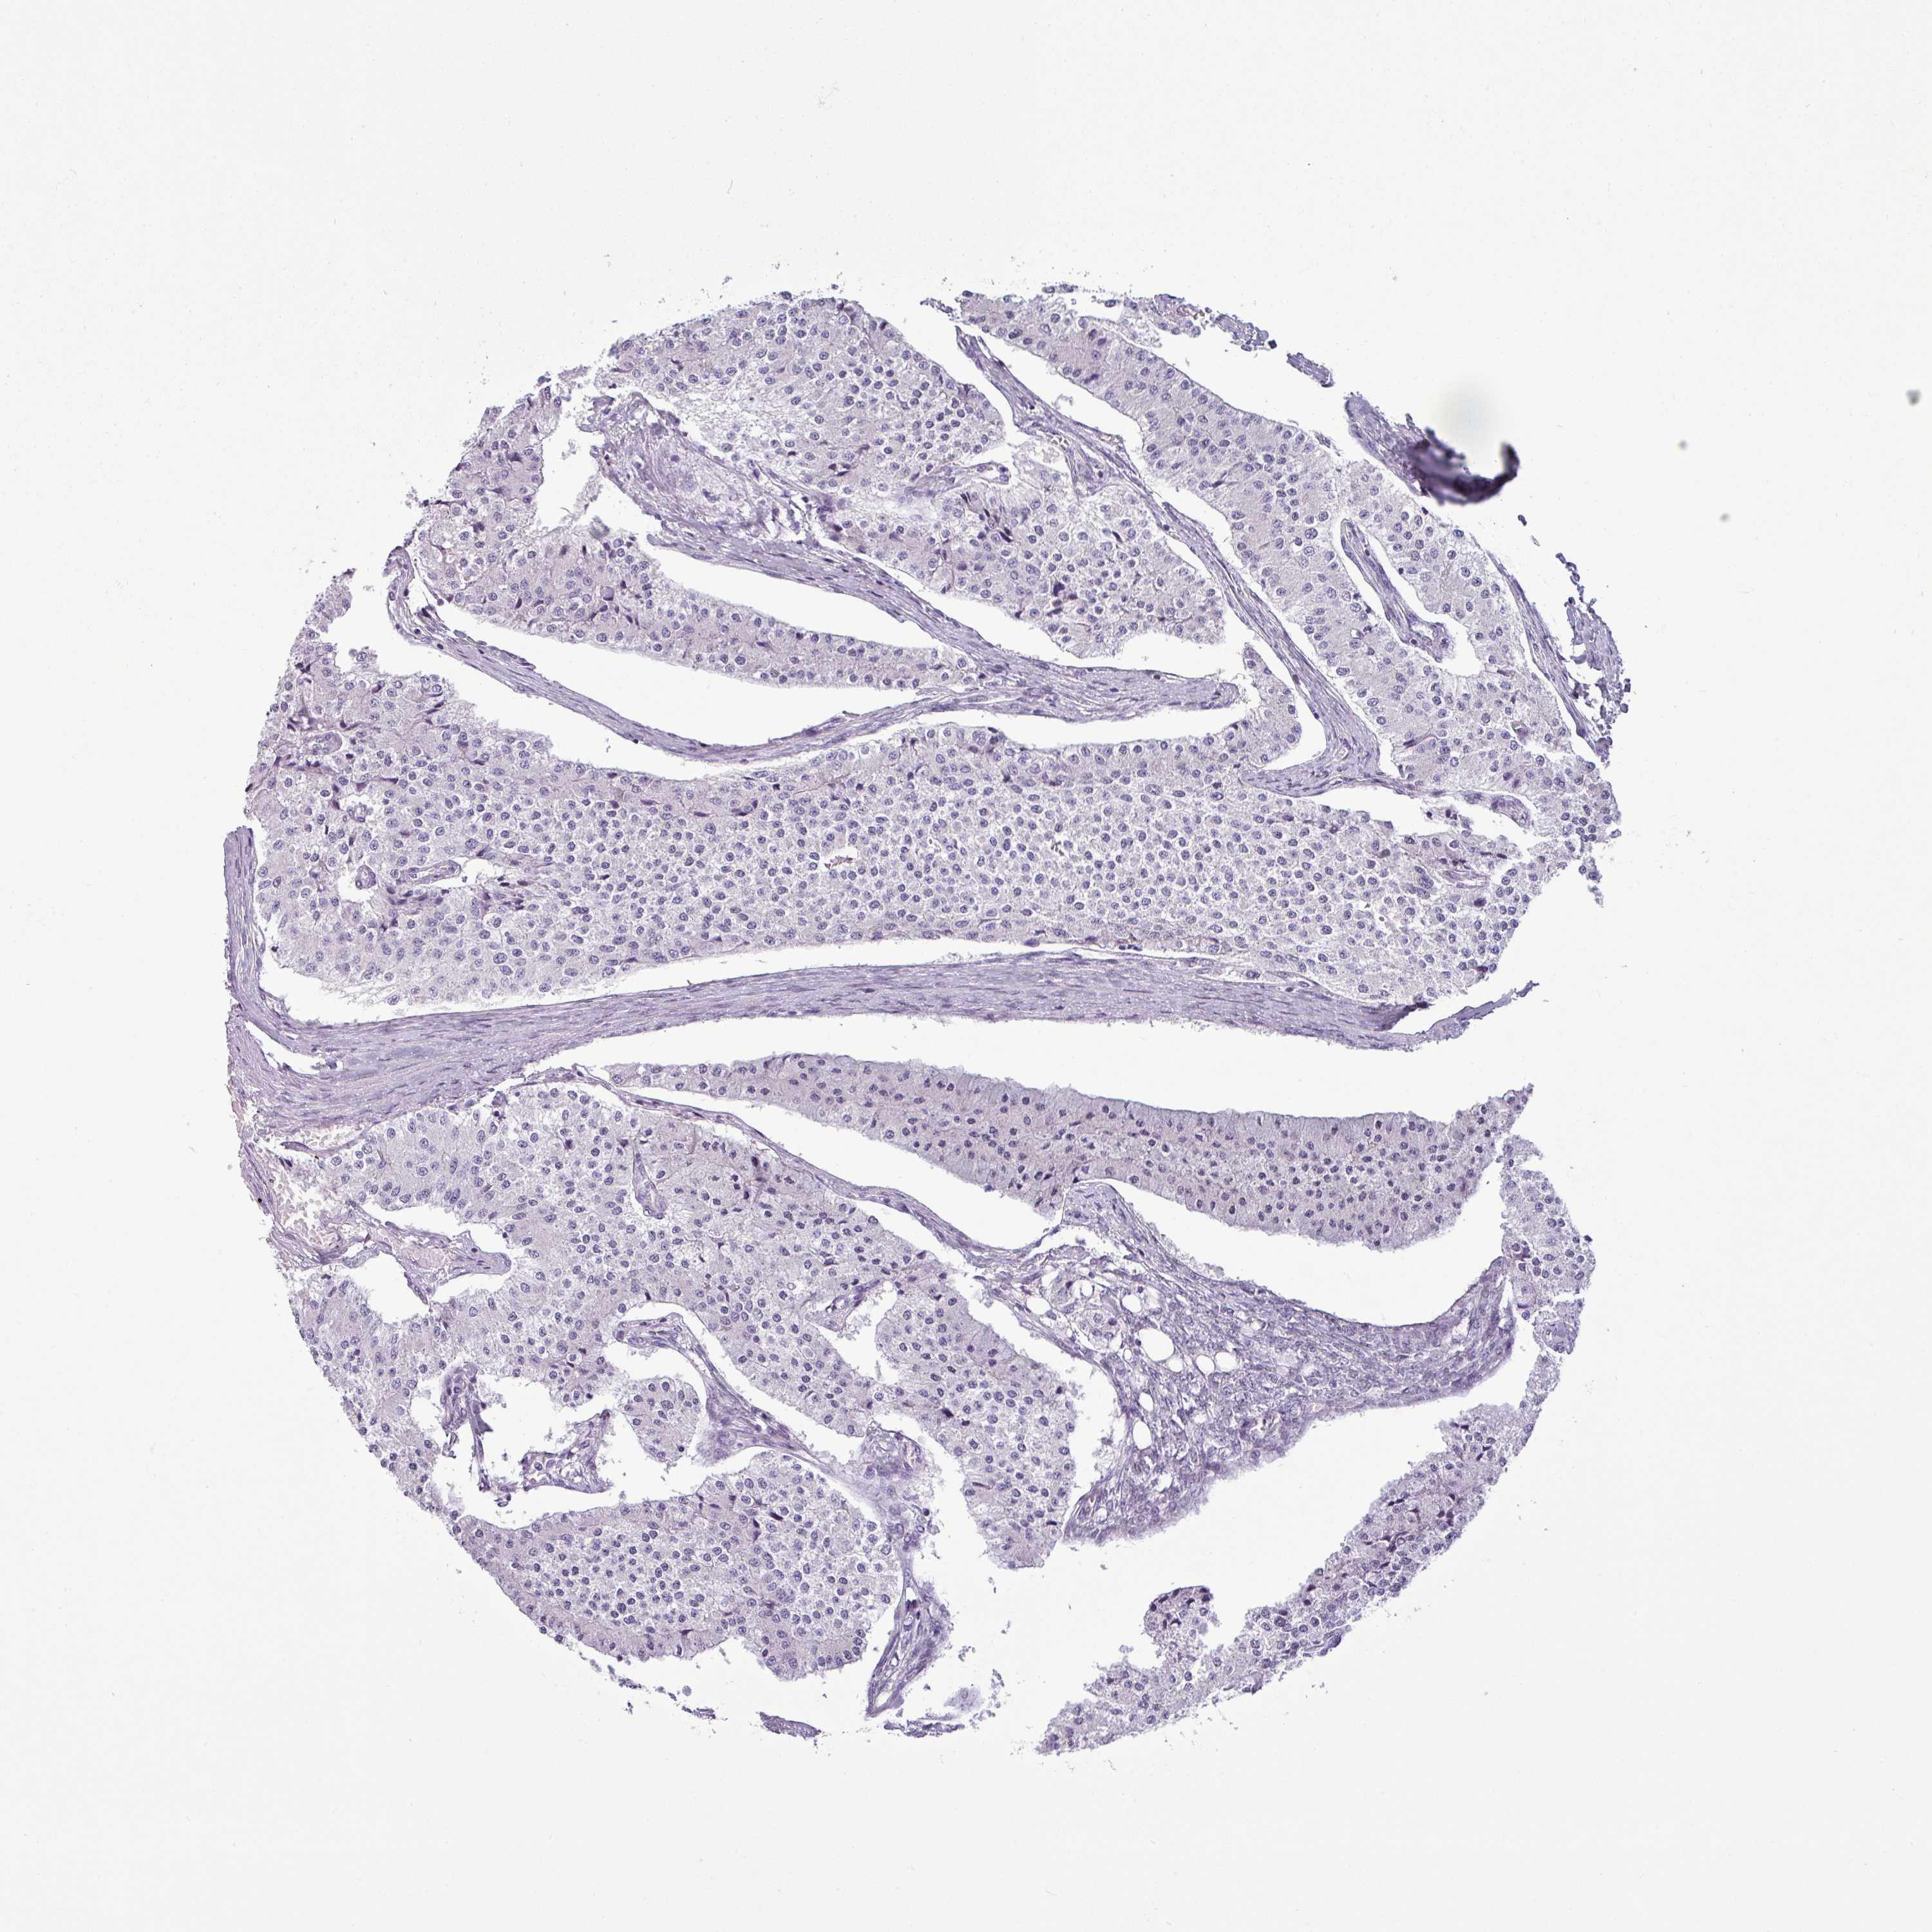

CARCINOID - Protein expressioni

A mouse-over function shows sample information and annotation data. Click on an image to view it in a full screen mode. Samples can be filtered based on level of antibody staining by selecting one or several of the following categories: high, medium, low and not detected. The assay and annotation is described here.

Each image is clickable and will lead to virtual microscopy that enables deeper exploration of all samples and also displays staining intensity scores, fraction scores and subcellular localization as well as patient and tissue information for each sample.

Antibody HPA036260

Staining

High

Medium

Low

Not detected

Intensity

Strong

Moderate

Weak

Negative

Quantity

>75%

75%-25%

<25%

None

Location

Nuclear

Cytoplasmic/membranous

Cytoplasmic/membranous,nuclear

Carcinoid, malignant, NOS

Carcinoma, NOS